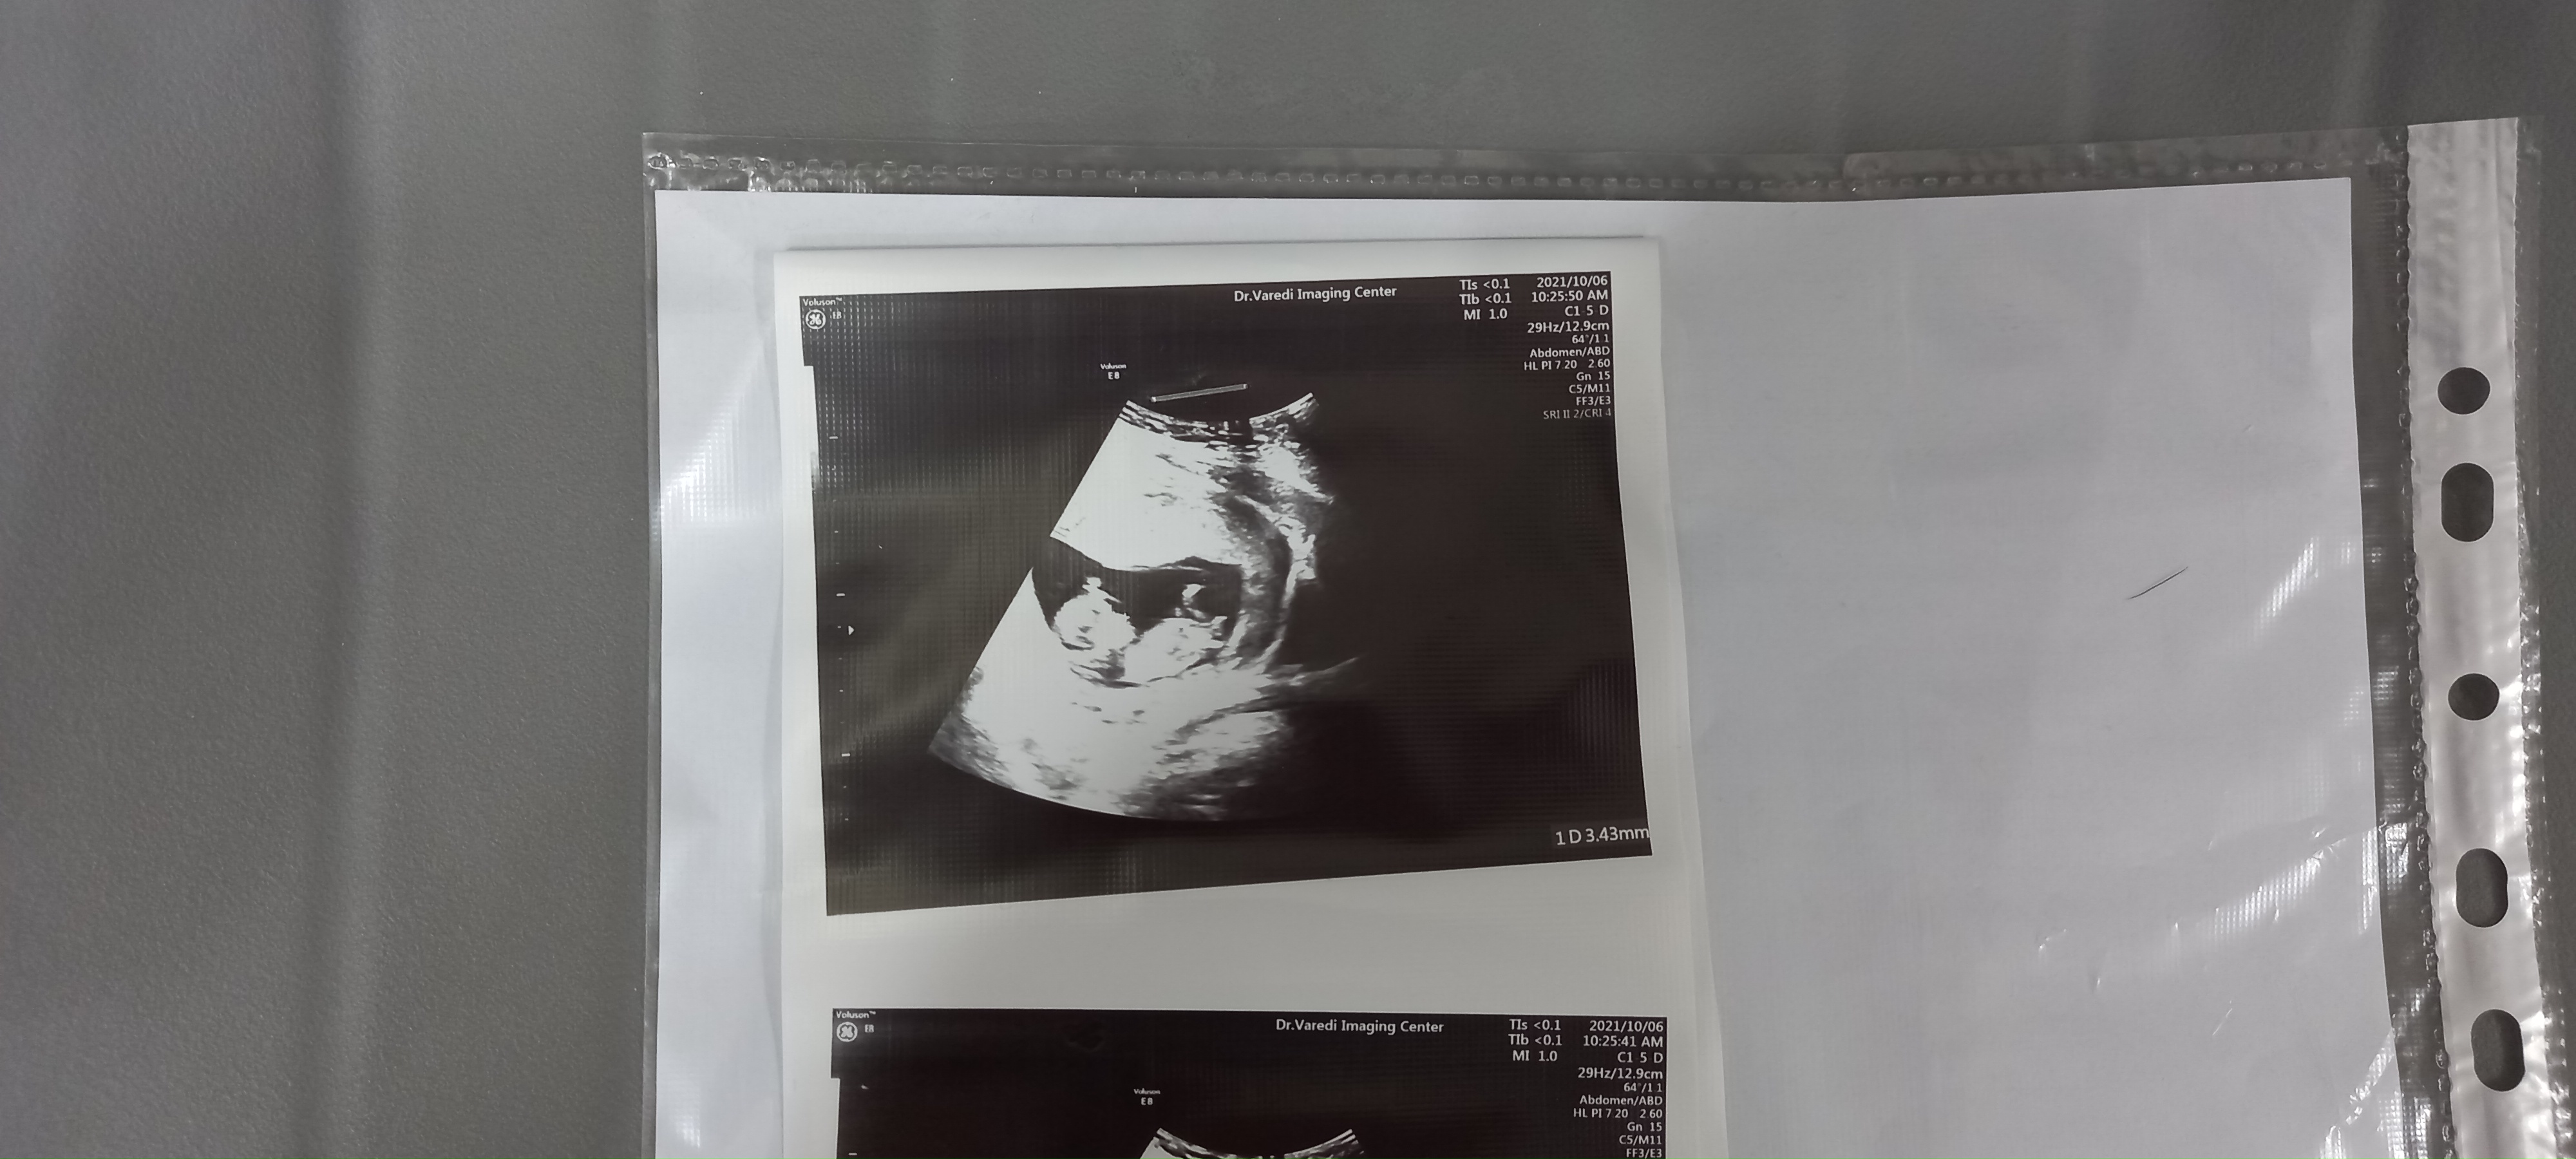

احتمال خیلی خیلی زیاد پسر

فک میکنم عکس نی نی من مثل عکس ان تی شماهستش الان دیدم

بیشتر به پسر شبیه

@مرجانaنوری هستی منم عکس بزارم نظر بدی